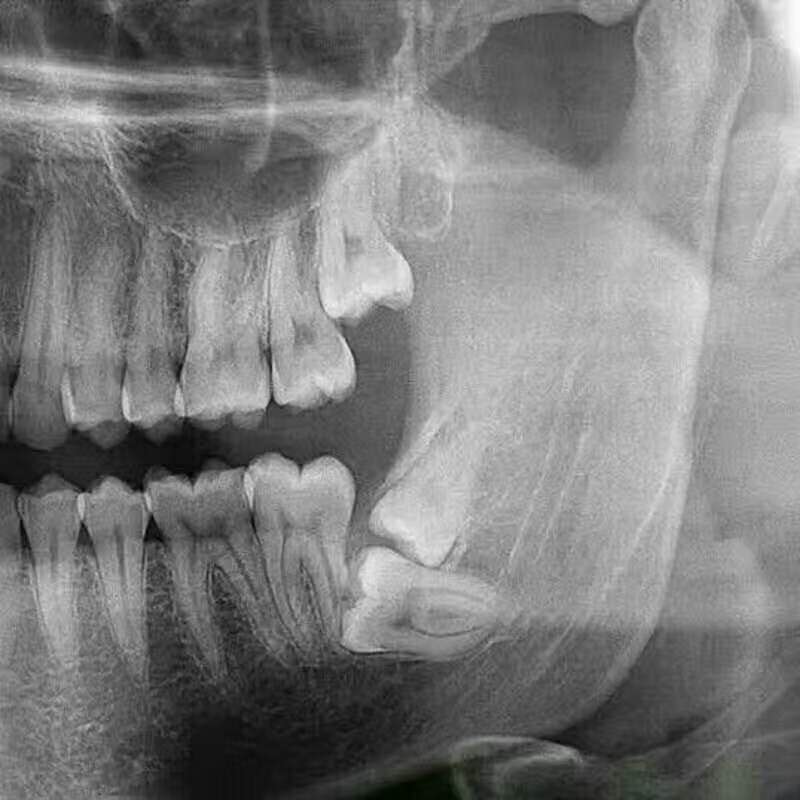

在青春后期,颌骨发育到接近成人大小。但有些人颌骨还不够大,没有足够位置供智齿萌出。智齿就会阻生在颌骨内,向其他方向生长。可能只有部分牙冠露出牙龈,或完全埋在颌骨里。牙根可能变形或向上颌窦或下颌骨神经所在部位生长,这很危险。如果智齿长不出来,横长在了,就叫水平阻生智齿,一般会挤到外边的牙,让外边的牙极度拥挤,容易牙疼。

智齿生长的位置特殊,给它的清洁和治疗带来许多问题,常引起的疾病有龋齿(俗称蛀牙)、牙周炎、牙髓炎:由于智齿在最里面,日常刷牙不容易清洁,容易产生蛀牙,且智齿往往由于萌发空间不足出现胀痛,还会侵犯邻牙,造成牙疼。由于没有对咬牙,有时智齿会过度萌发,进而影响咬合;还有时会萌发不足成为阻生齿,引起牙列不齐,冠周间隙感染,张口困难。智齿是第三大臼齿,对相邻的第二磨牙有重要影响。由于大多数智齿是前倾阻生的,约呈45度角顶在第二磨牙上,从而形成一个牙冠夹角,容易嵌塞食物,久之导致第二磨牙龋坏,甚至牙髓炎,就算没有那么严重也会影响第二磨牙的寿命。